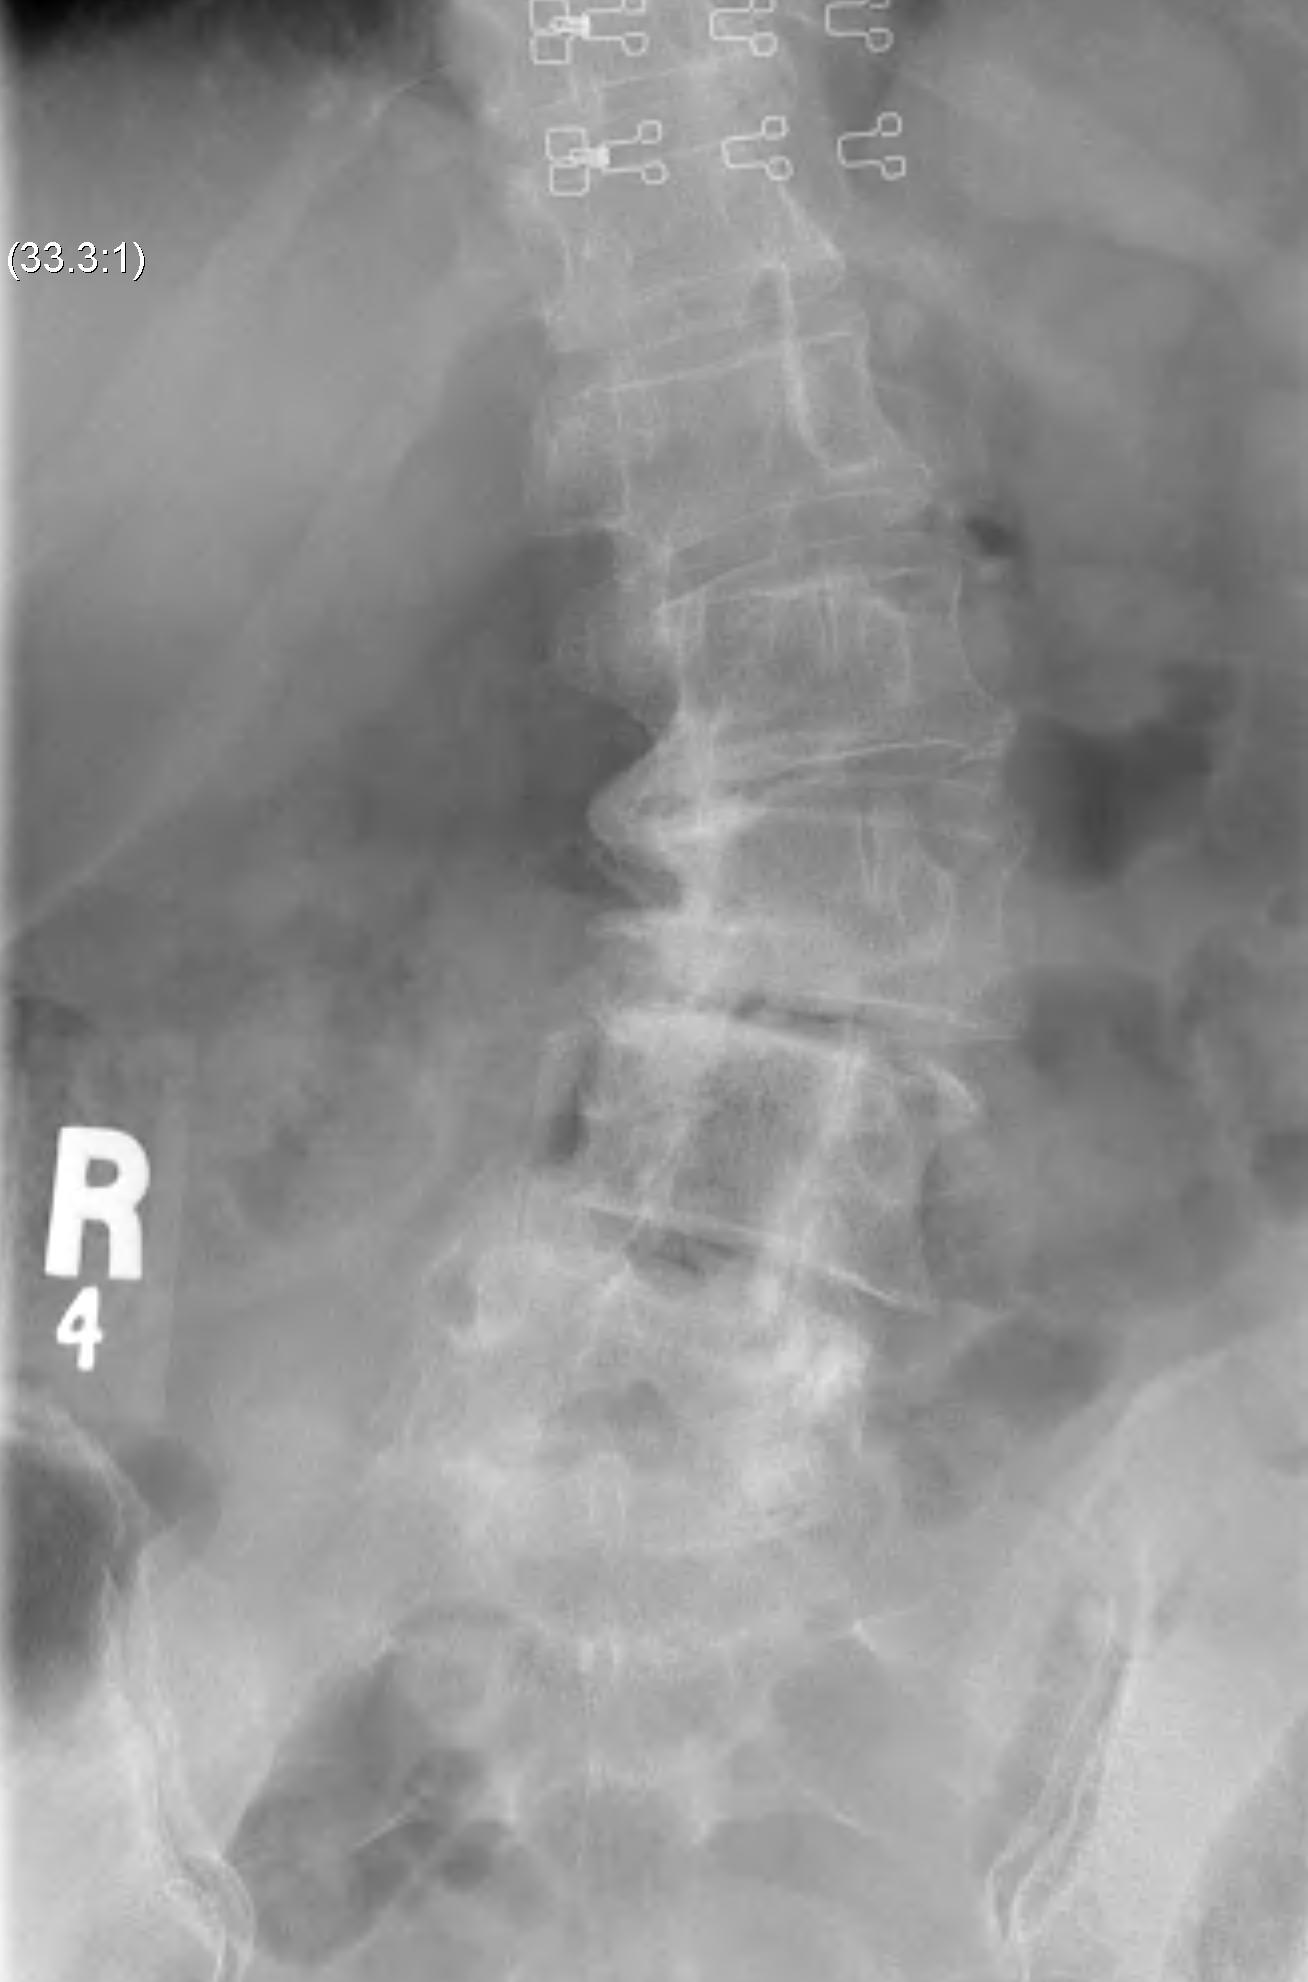

X-ray